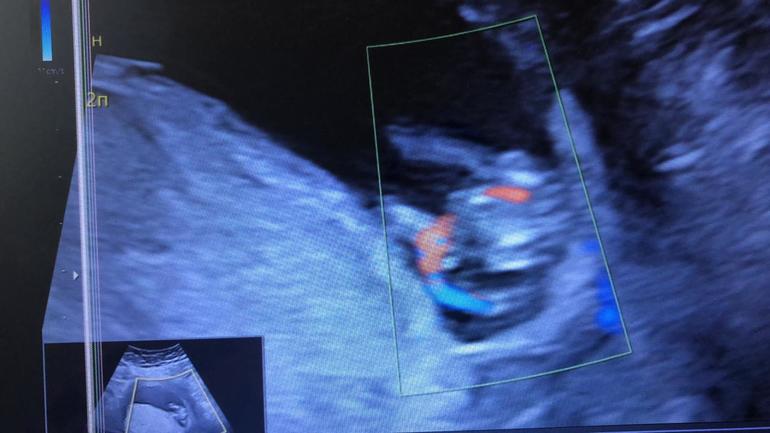

Полип ЦК на 19 неделе Пройден второй скрининг, закрашиваю кружок.